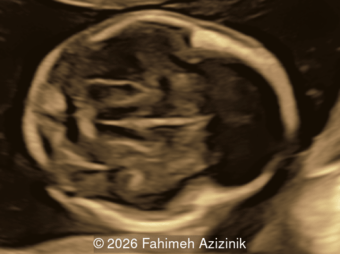

A 35-year-old secundigravida was referred to our unit at 20 weeks gestation for evaluation of suspected fetal skeletal abnormalities. Her first child was healthy, and her personal and family history were otherwise unremarkable. Two years later in a subsequent pregnancy, the patient presented for ultrasound evaluation. This examination was performed at 13 weeks of gestation and demonstrated the following findings: